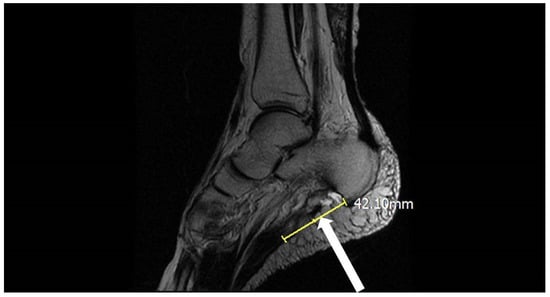

2. Case Presentation